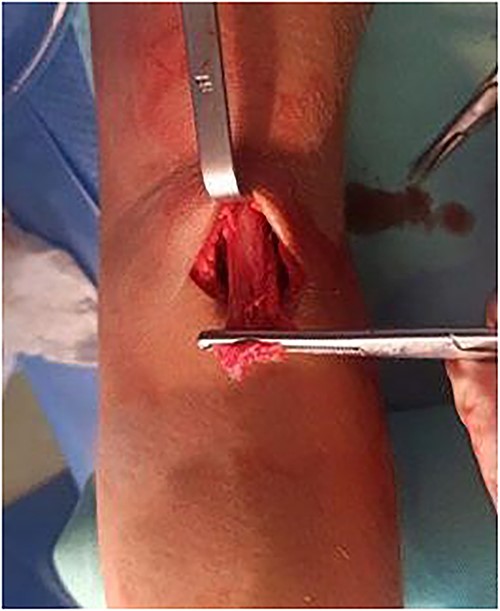

Given this clinical presentation, surgical treatment was recommended for tendon repair. A single-incision technique with fixation using two suture anchors was employed (Figs 5 and 6), following the method described by Maciel et al. [13]: An ~5 cm access incision was made in the anterior region of the proximal third of the forearm in a transverse plane. With the forearm in complete supination and at a 10-degree elbow flexion, two suture anchors were positioned, loaded with high-strength threads, into the radial tuberosity. Fixation of the distal anchor repair was performed first to establish tendon length, followed by fixation of the proximal anchor repair to maximize the tendon-to-bone contact area. Intradermal skin suturing performed.